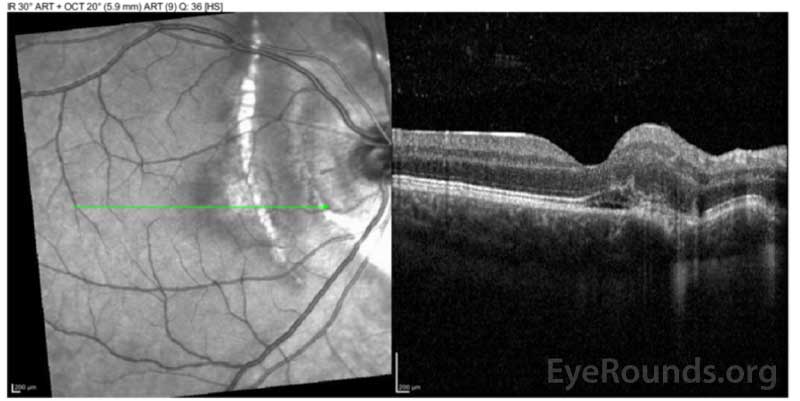

Optical coherence tomography (OCT) of the right eye that shows pre-retinal hyperreflective vitreous

Figure 3: Optical coherence tomography (OCT) of the right eye that shows pre-retinal hyperreflective vitreous; areas of discontinuity in the retinal pigment epithelium just nasal to the fovea and in the peripapillary area, consistent with choroidal ruptures; and sub-foveal outer retinal atrophy.